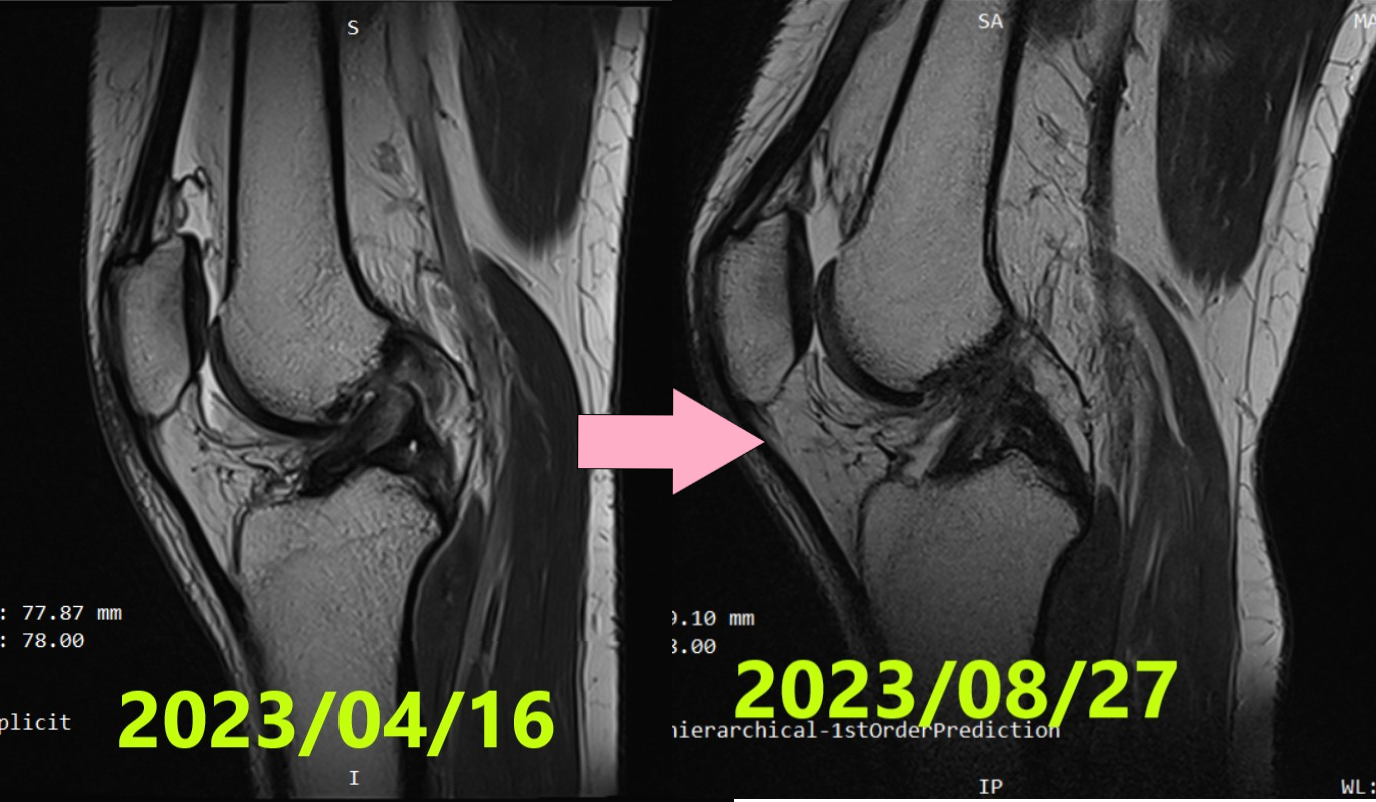

Caso 50 | Curación Natural del LCA: De la Grave Ruptura Ihara IV a la Regeneración Perfecta (ACLOAS 0)